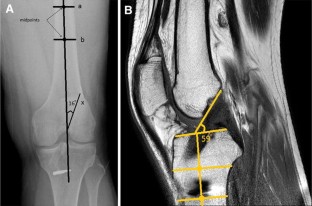

Fig. 1

5. Papannagari R, Gill PJ, Defrate LE, Moses JM, Petruska AJ, Li G (2006) In vivo kinematics of the knee after anterior cruciate ligament reconstruction: a clinical and functional evaluation. Am J Sports Med 34:2006–2012

24. lllingworth KD, Hensler D, Working ZM, Macalena JA, Tashman S, Fu FH (2011) A simple evaluation of anterior cruciate ligament femoral tunnel position: the inclination angle and femoral tunnel angle. Am J Sports Med 39:2611–2618